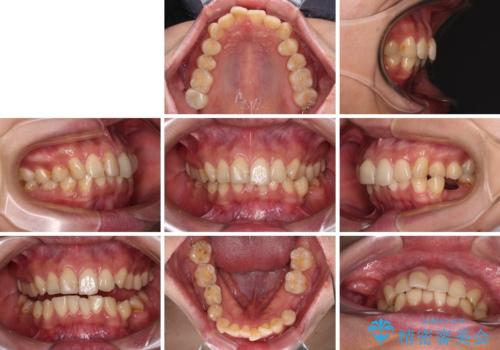

- 全体的なデコボコと左下乳歯部の欠損を気にして来院された患者様です。

乳歯が抜け落ちた後の後続永久歯が欠損しているため、スペースが残っておりました。

口元の突出感を気にしているのであれば欠損スペースを利用して抜歯矯正を行うことも可能ですが、横顔の印象はスッキリとしている状態であったため、矯正治療でスペースを閉じきることは不可能と判断し、インプラントによる補綴治療を行うこととしました。

第二小臼歯の欠損によるが乳歯残存や欠損が多く、この乳歯は後続永久歯に比べて幅が非常に大きいため、教聖地料によるスペースクローズが難しいことが一般的です。